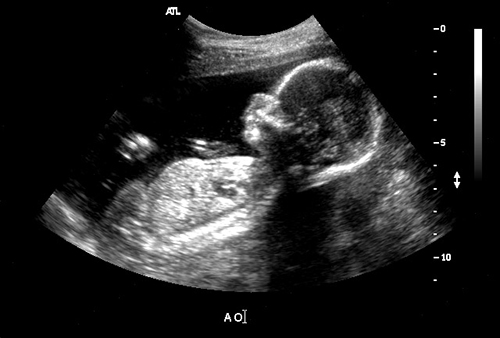

Российские специалисты смогли проследить за развитием мозга плода в утробе матери

Как предает "Российская газета", это стало возможно благодаря совместной разработки Международного томографического центра (МТЦ) Сибирского отделения РАН, Томского государственного университета и Университета Вашингтона (США).

В основе лежит новый метод макромолекулярной протонной фракции (МПФ). Он показывает степени миелинизации головного мозга плода на самых начальных этапах. То есть, насколько хорошо защищены и функционируют мозговые цепи. Миелин - это многослойные клеточные мембраны, окружающие нервные отростки (аксоны). Процесс его формирования начинается примерно с 18-20 недели развития плода и продолжается приблизительно до 10 лет. Определение миелинизации мозга позволяет выявить отклонения в развитии плода.

В частности, подобные отклонения связаны с психическими недугами вроде аутизма и шизофрении. В отчете ученых говорится: "Основная идея нашего метода - специальная математическая обработка изображений. Алгоритм позволяет видеть сигналы, которые происходят от клеточных мембран. Технологический прорыв заключается в реконструкции карты МПФ с использованием исходных данных, которые могут быть получены практически на любом клиническом томографе.

У нас появился новый инструмент, который может давать информацию о том, насколько своевременно идет созревание мозга. Пока мы работаем с плодами, потому что у нас есть уникальная в России возможность собирать подобную информацию. В будущем мы планируем подключить еще исследование развития мозга в детском возрасте, чтобы получить полную картину пре- и постнатального процесса миелинизации".